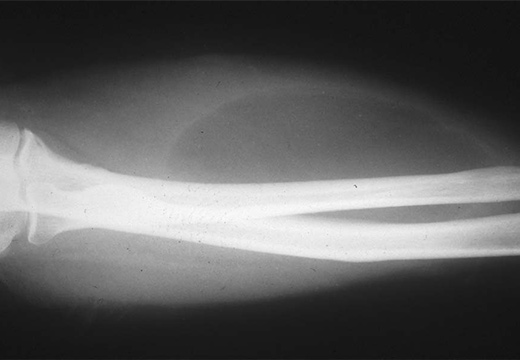

На рентгене

Обследование показано при диагностике шишек, расположенных на внутренних органах, в кардиодиафрагмальном углу, загрудинном пространстве и в средостении.

Жировик определяется на рентгене как световое пятно с четкими краями. Форма может быть разной: грушеобразная при кардиодиафрагмальной опухоли, полукруглая при абдоминомедиастинальном уплотнении. Показатель зависит от степени компрессии.

На снимке при диагностике можно увидеть мелкие включения – фиброзные тяжи, кальцинаты. Во время исследования органов ЖКТ в брюшную полость вводят газ. Это позволяет оценить степень подвижности.

Для определения размеров и других параметров рентгеновские снимки делают в нескольких проекциях. При подозрении образования, локализованной в области мозга целесообразнее провести МРТ.